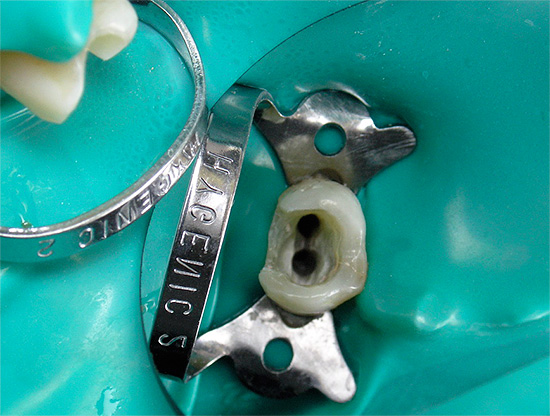

Poiché la pulpite cronica è una forma irreversibile di infiammazione dei tessuti molli, quando non possono più essere immagazzinati nel dente, vengono spesso utilizzati per il trattamento estrazione completa della polpa da tutti i canali dentali. Lo stesso approccio è seguito nel trattamento della pulpite cronica nella fase acuta.

Nell'odontoiatria moderna, viene data preferenza al metodo di estirpazione (estrazione) vitale del "nervo". Durante il trattamento delle forme croniche di pulpite o delle sue esacerbazioni, viene utilizzata solo l'anestesia senza fondi aggiuntivi per la devitalizzazione (uccisione) della polpa.